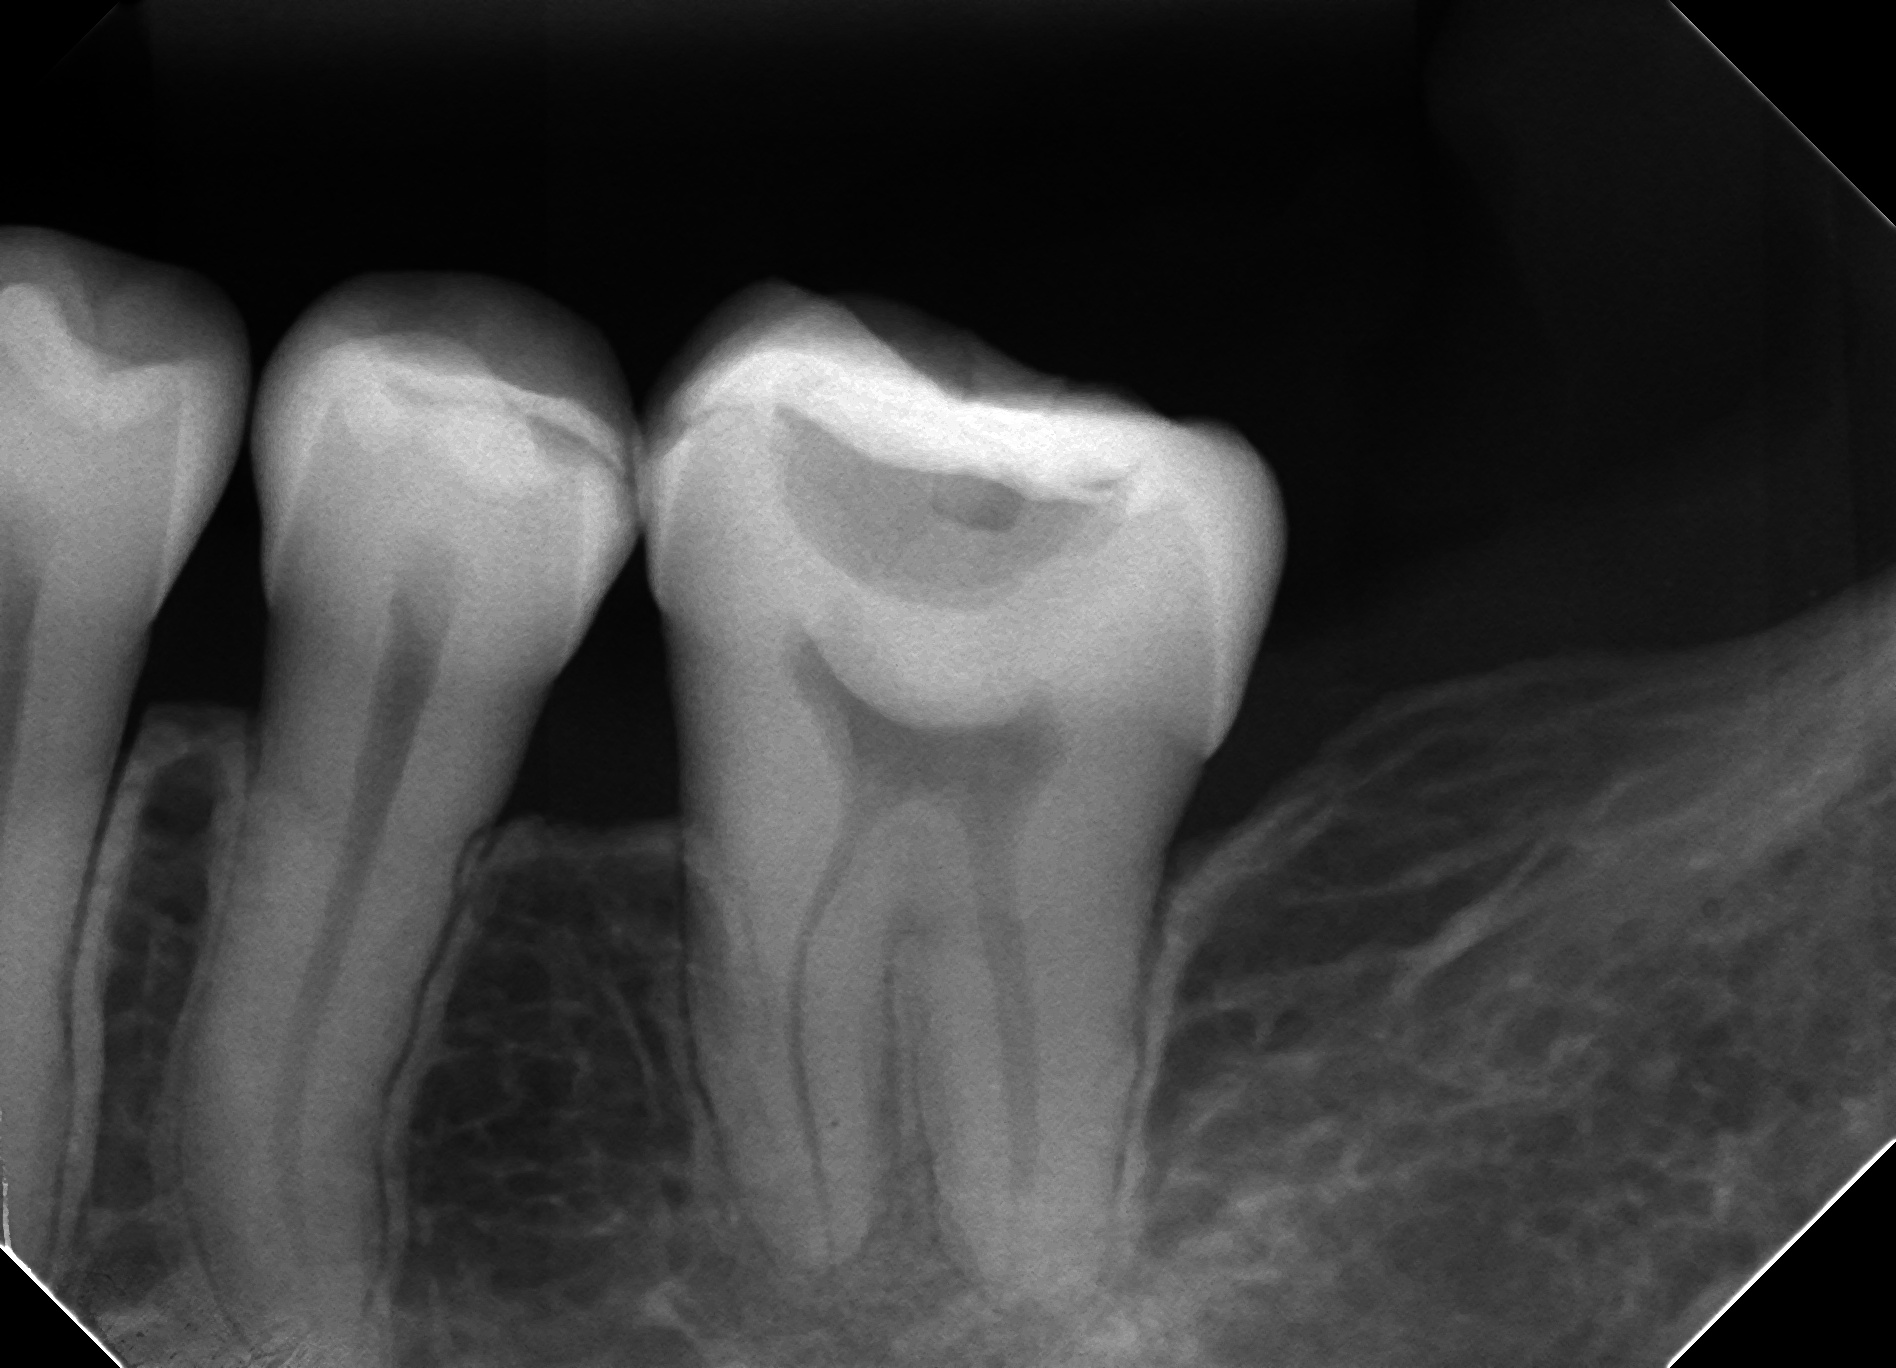

初診時PA

#18は第二大臼歯だが、矯正で#19の位置に#18を移動したという。

なのでこの歯は虎の子の歯だ。